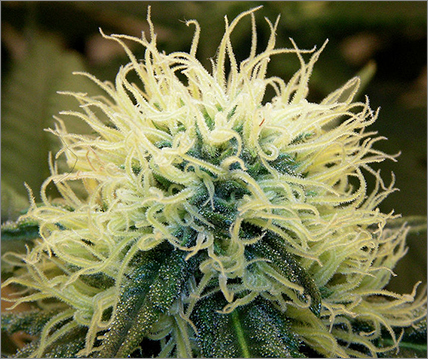

2 Cannabis stave off HIV

“The Journal of Leukocyte Biology” published a discovery involving the use of Tetrahydrocannabinol, more commonly known as THC in marijuana, to impair the most common and widely found strain of Human immunodeficiency virus (HIV). When the virus was injected into the white blood cells that defend the immune system, then exposed to THC, it was discovered that the cells actually increased their ability to fight against the virus.